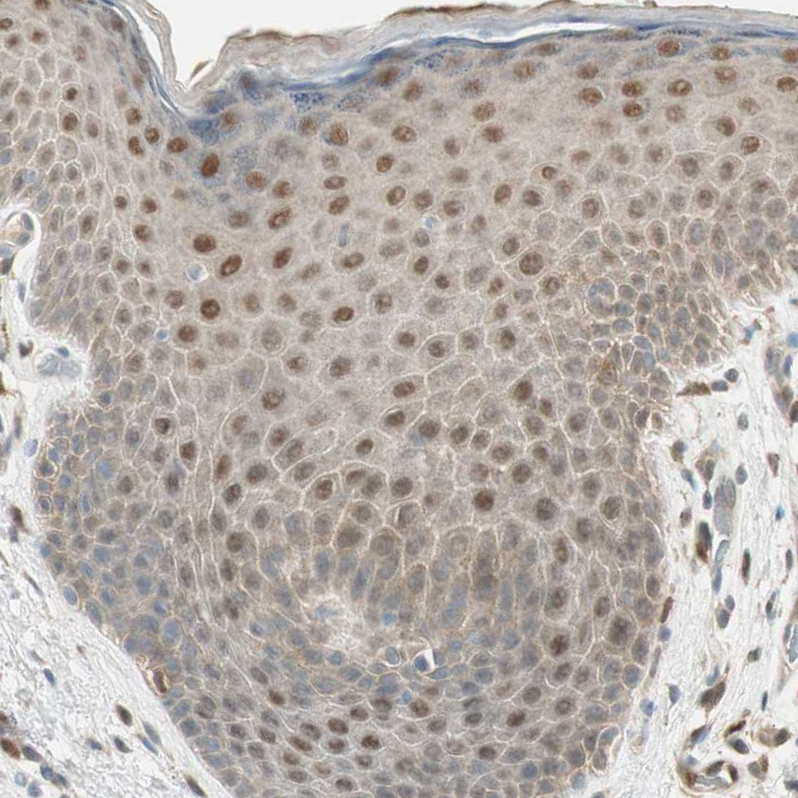

Immunohistochemical staining of human lung shows strong cytoplasmic and nuclear positivity in macrophages.